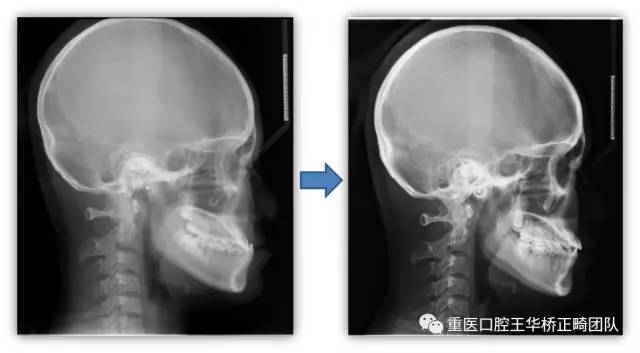

头颅侧位片的对比